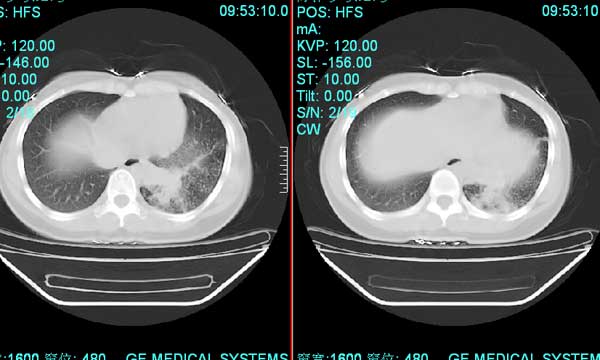

以下是引用pujunzhi在2008-7-1 20:03:00的发言:[br]支持楼主意见!两肺继发性肺结核伴多发空洞形成。